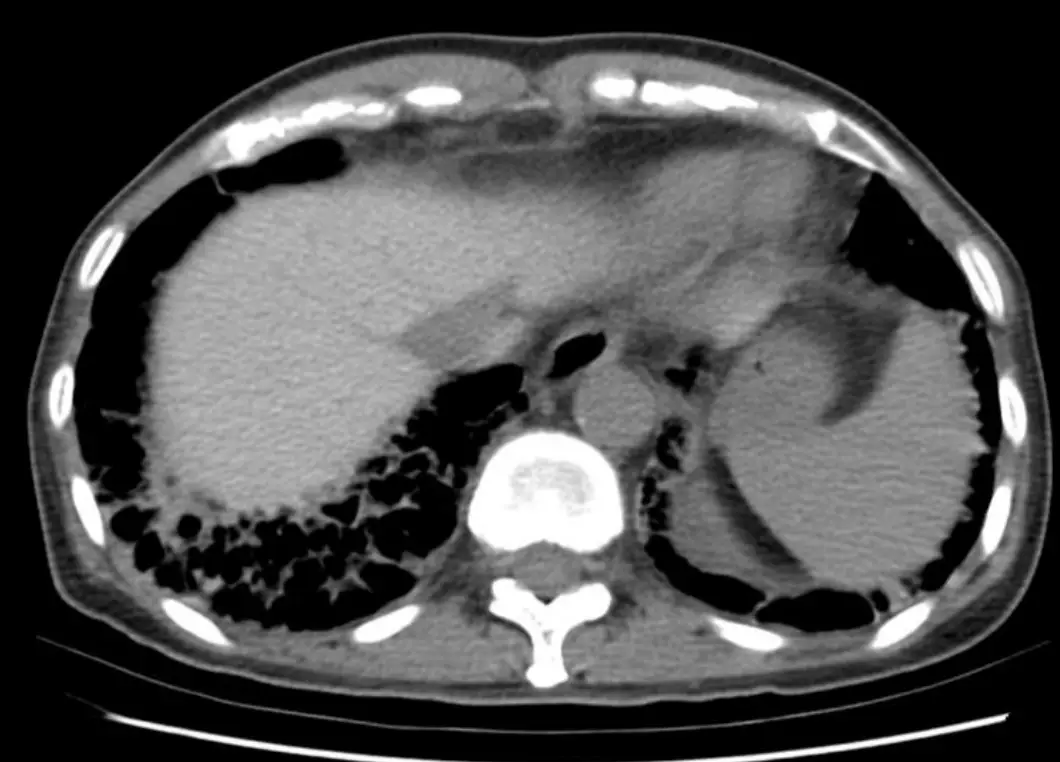

圖二(腹部電腦斷層,無顯影劑): 此圖是本題最關鍵的影像。肝臟實質(右側大葉)在無顯影劑的情況下呈現明顯高衰減(high attenuation / hyperdense),亮度遠高於正常肝臟,甚至較脾臟更亮。這是 Amiodarone 及其代謝物(desethylamiodaro